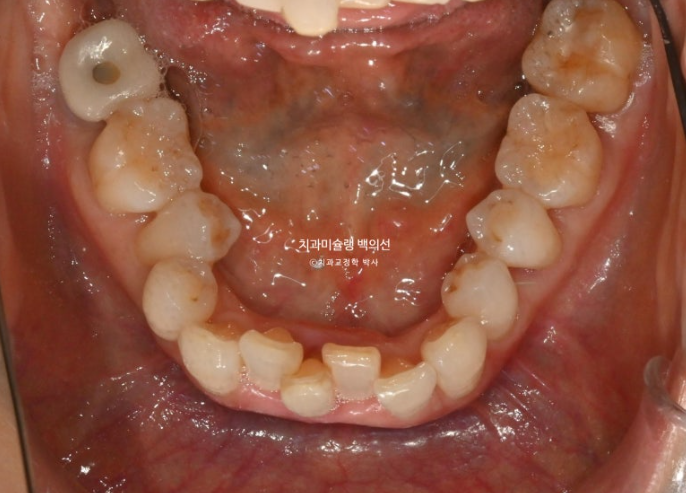

1년 전 치아 틀어짐이 점점 심해지면서 찾아오신 50대 환자분

예전에는 입이 편하게 다물어졌었는데 치아가 틀어지고 벌어지고 내려오면서 이제는 입이 편하게 안 다물어지는 것도 불편한 상태입니다.

파란 화살표 치아는 잇몸이 검붉게 보입니다.

엑스레이상 이미 치주염이 상당히 진행이 되어 발치가 불가피한 상황이였습니다.

위 앞니는 잇몸이 꽉 잡아주지를 못해서 점점 솟아 내려오고 튀어나오면서 치아사이가 벌어졌습니다.

작은어금니도 안으로 쓰러져 있어서 이 부분은 윗니와 엇갈려 물리는 가위교합 입니다.